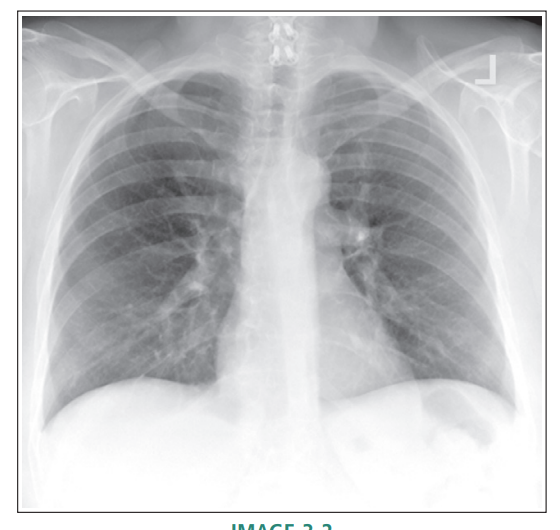

Inferior sagittal plane tilted towards IR

Right thorax rotated posteriorly

Right thorax rotated anteriorly